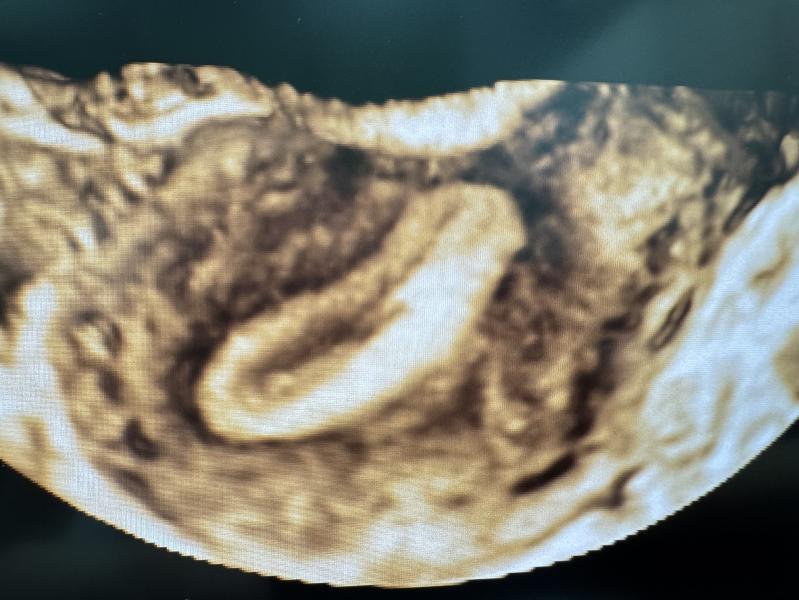

На снимке кстати пациентка, 2 кесаревых сечения, рубец до 20мм, тоненький. Планировать беременность пока не собирается.